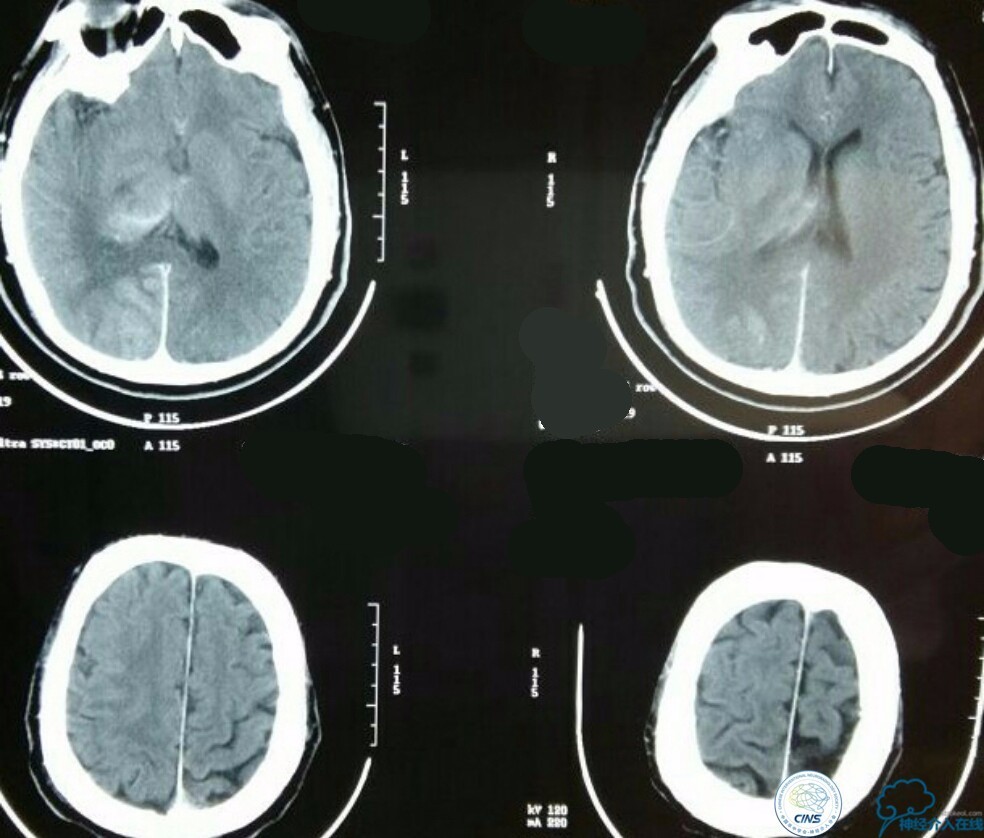

术后生命体征平稳,成功撤呼吸机,肌力较前好转,复查头颅CT:

右侧丘脑高密度影,右侧枕叶可能也有梗死,祈祷慢慢恢复吧!